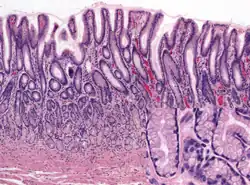

Histology of normal antral mucosa. Antral mucosa is formed by branched coiled tubular glands lined by secretory cells similar in appearance to the surface mucous cells. H&E stain.

Glands differ where the stomach meets the esophagus and near the pylorus.[26] Near the gastroesophageal junction lie cardiac glands, which primarily secrete mucus.[25] They are fewer in number than the other gastric glands and are more shallowly positioned in the mucosa. There are two kinds - either simple tubular glands with short ducts or compound racemose resembling the duodenal Brunner's glands. Near the pylorus lie pyloric glands located in the antrum of the pylorus. They secrete mucus, as well as gastrin produced by their G cells.[27]